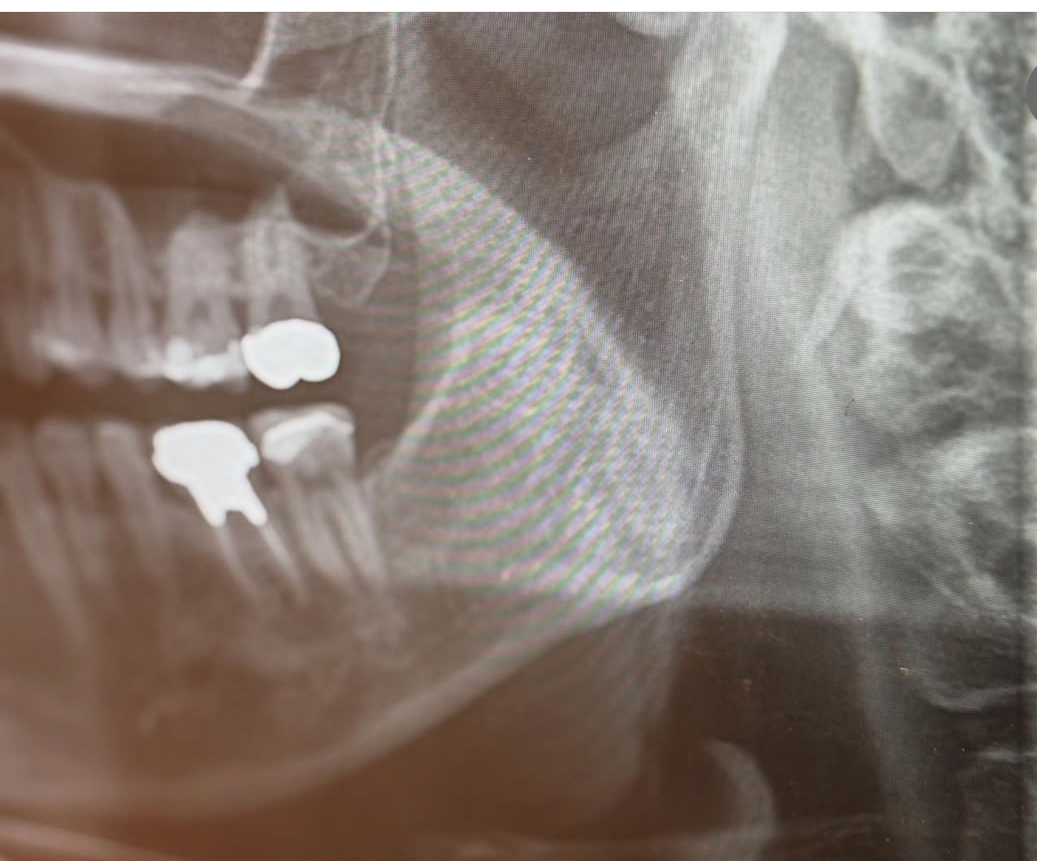

当院では、受診時に日頃撮影するレントゲン写真(歯科用パノラマエックス線写真)に写る下顎の骨の状態を確認し、骨粗鬆症の可能性が考えられる方に対して、医科(整形外科等)へのご紹介を行う医科歯科連携の取り組みを行っています。

歯科のレントゲン検査では、歯や顎の診査に加えて、下顎の皮質骨の状態を通じて、骨の健康状態の一端を把握できる可能性があります。